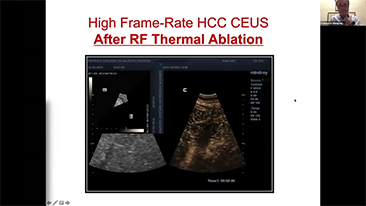

Bir karaci?er ne kadar net g?rĂŒlebilir?

Hemanjiyom veya karaci?er kanseri gibi fokal karaci?er lezyonlar? i?in, ultrason kontrast g?rĂŒntĂŒlemesi ?nemli bir rol oynar. Ultra geni? lineer olmayan UWN+ kontrast g?rĂŒntĂŒleme teknolojisi, daha dĂŒ?ĂŒk MI ve daha uzun perfĂŒzyon sĂŒresi g?zlemi ile daha iyi penetrasyon, daha yĂŒksek kontrast doku oran? elde edilmesine yard?mc? olabilir.